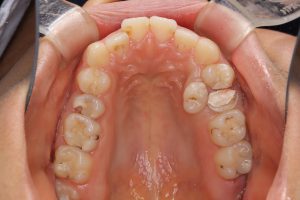

来院した時はまだ10代の患者さんでしたが、むし歯が多く、左上の2本の小臼歯にもむし歯が認められ、後方の第2小臼歯は歯髄(神経)に達する程進行していました。そして、内側には過剰歯が存在していました。

下の写真は治療中のものです。